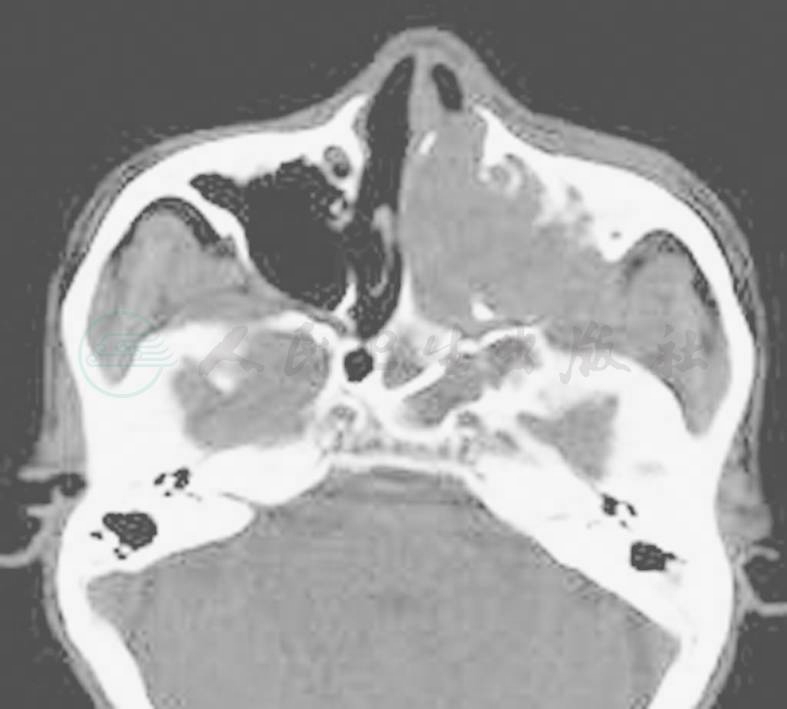

图3-11左侧上颌窦鳞癌CT表现

左侧上颌窦内软组织肿块伴骨质破坏

可见鼻腔及鼻窦内不规则等密度软组织肿块,密度较为均匀,边缘模糊,肿瘤较大时可有不规整的斑点状低密度坏死区,肿块中有时可见有残存骨片。90%以上患者有不同程度骨质破坏,最常见为鼻腔内侧壁、外侧壁破坏伴鼻腔内软组织肿块(图3-11)。肿瘤向周围浸润,表现为局限或广泛骨质破坏和软组织肿块,肿块呈侵袭性生长,直接侵犯眼眶、翼腭窝、面部软组织等邻近结构,如上颌窦后方脂肪被肿瘤占据,则表明癌肿侵入颞下窝和翼腭窝。